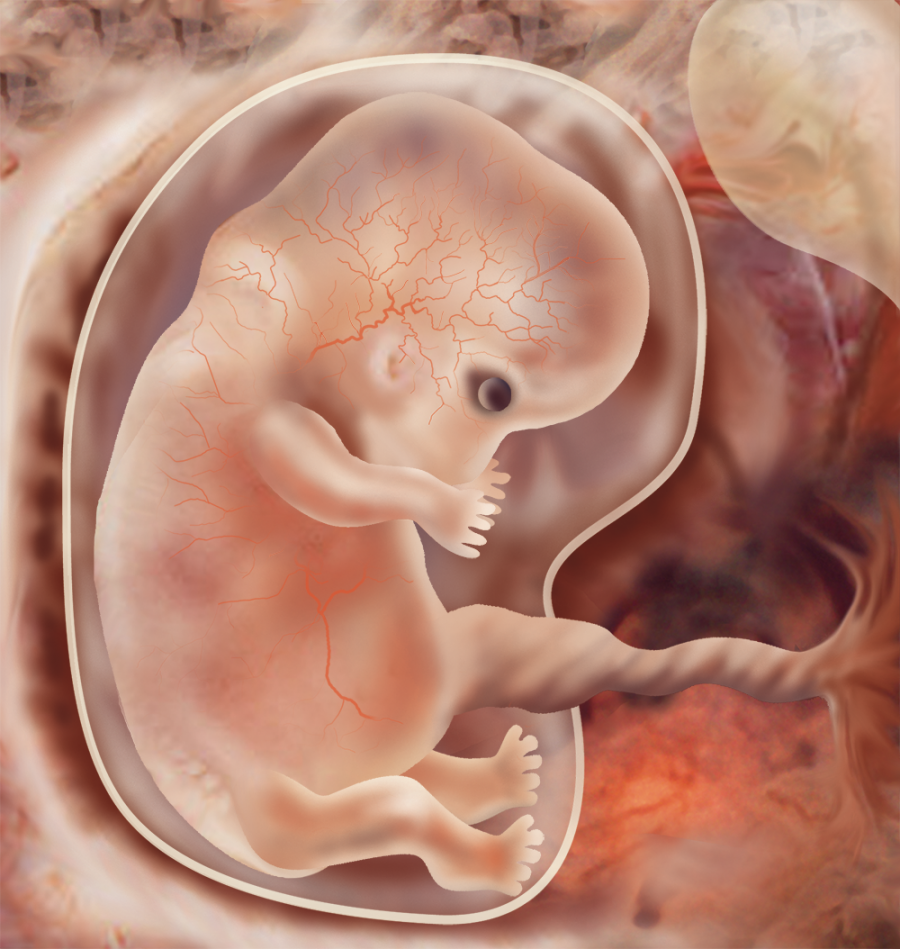

Зарождение жизни: Фотографии Леннарта Нильсона